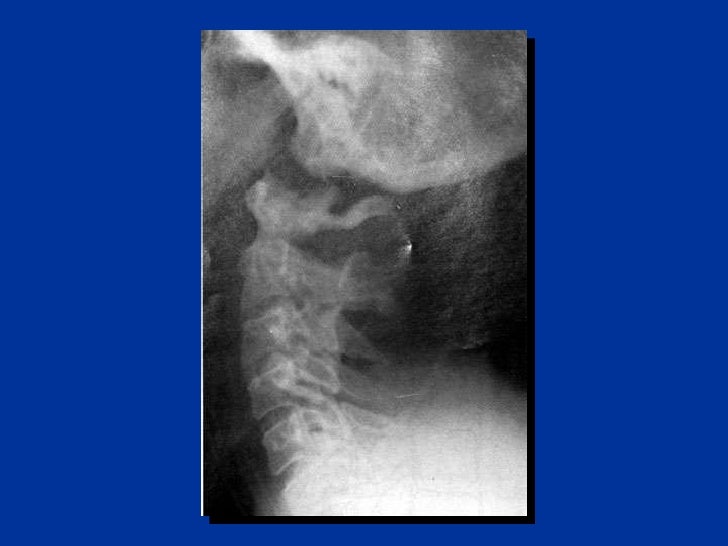

X-ray consists of a three view cervical x-ray series, adding a swimmer's view if the lateral doesn't include the C7/T1 interface.

CT scan or X-ray images are evaluated for the presence or absence of directly visible fractures. In addition, indirect signs of injury by the vertebral column are incongruities of the vertebral lines, and/or increased thickness of the prevertebral space: